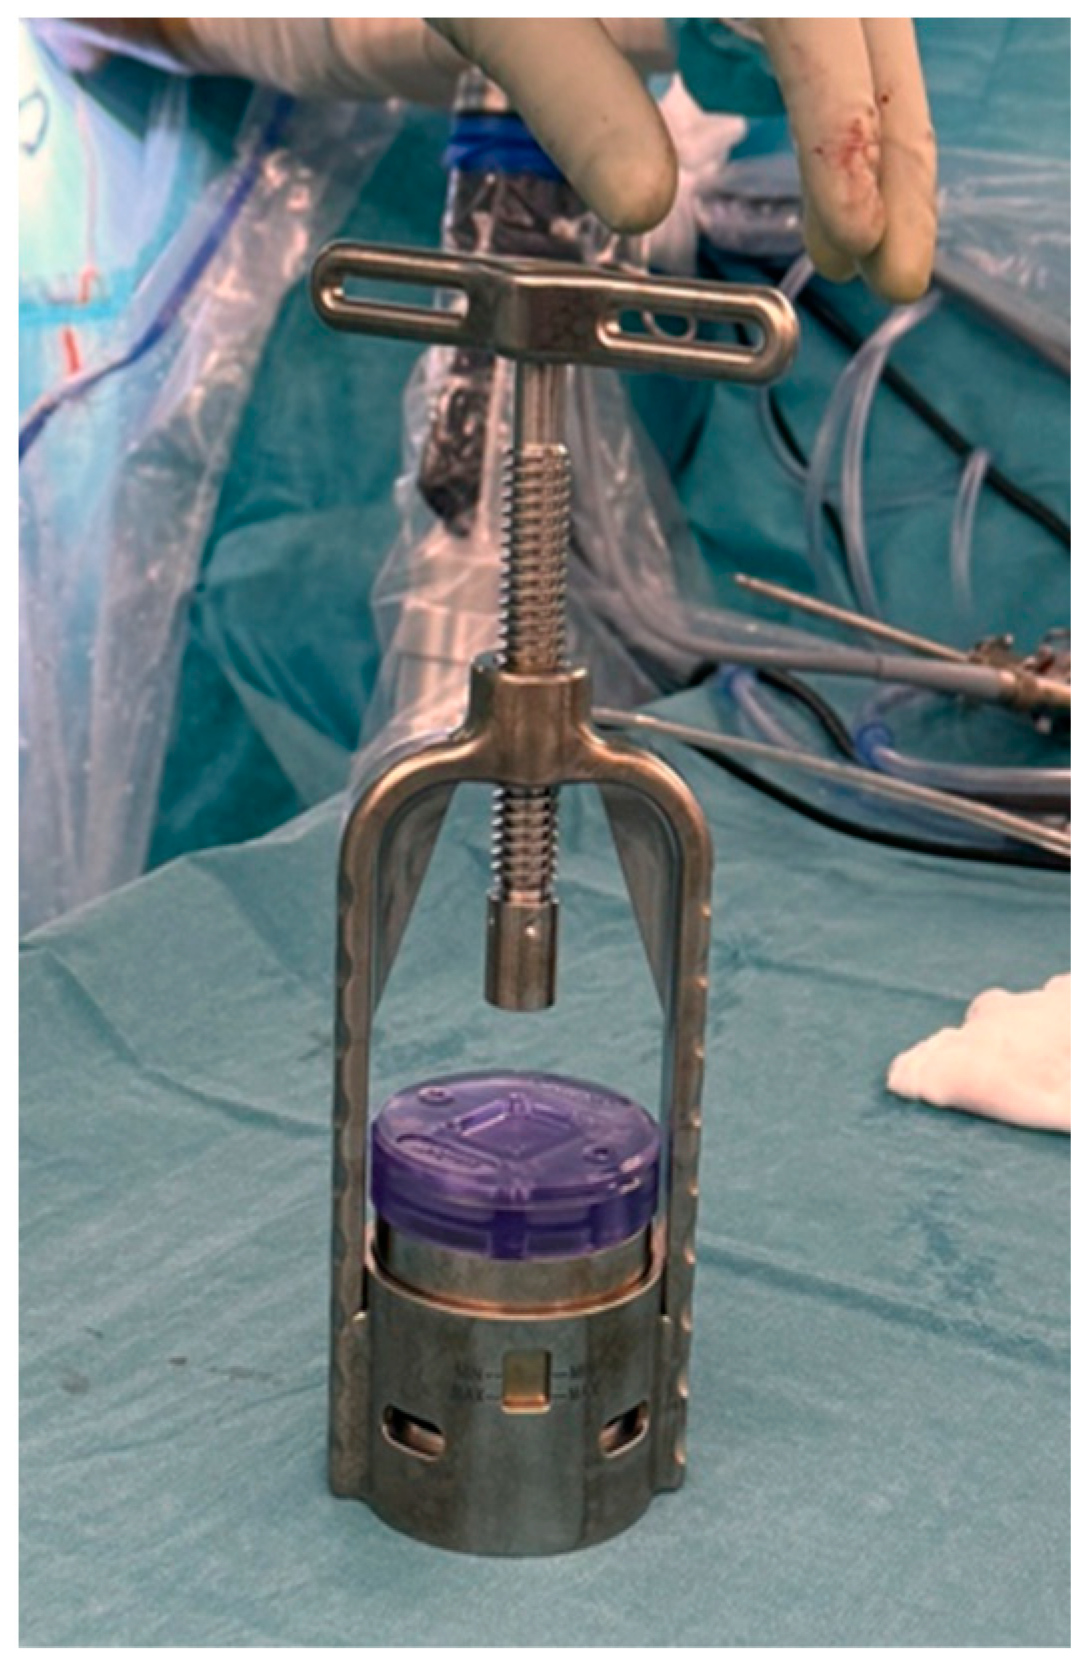

3.1.4. The Future of Patch Augmentation

3.1.6. Bioresorbable Scaffolds